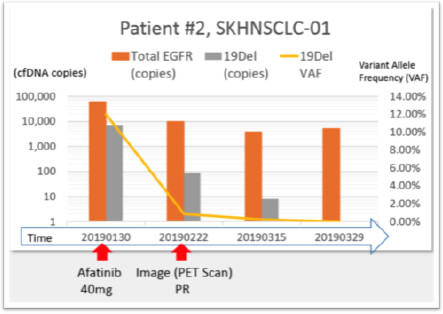

User Story #2

Patients with Lung Cancer Due to Exon 19 mutation in EGFR

- Exon 19 deletion was detected from patient’s tissue using qPCR

- Deletion was confirmed using patients’ blood sample using MoDEL™